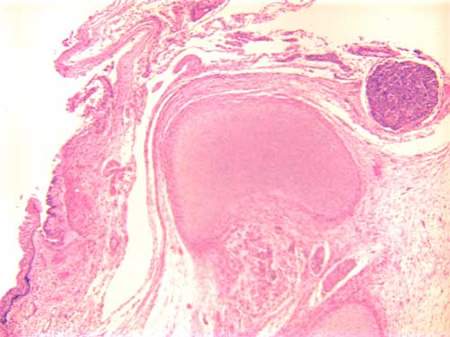

Figure 4: Incomplete formation of

vertebral body with primitive neural

tissue in continuity with squamous

epithelium at higher power

A lumbrosacral myelomeningocele is confirmed. The vertebral body is incomplete at the point of the defect. The squamous epithelium is not continuous overlying the vertebral column; instead there is immature neural tissue in continuity with the squamous epithelium.